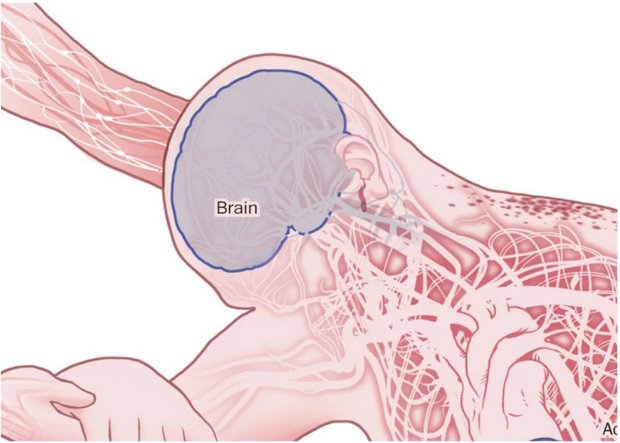

مایع در مغز تجمع می یابد. تشنج باعث گسترش خون عفونی و سایر مایعات بدن بیمار می شود.